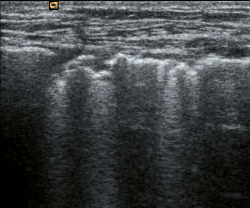

Échographie pleurale

L'échographie pleurale est un examen médical. Il s'agit d'une échographie du thorax explorant les anomalies de la plèvre, en particulier les épanchements pleuraux[1], et du poumon. Au cours de l'examen, il est également possible de réaliser une ponction écho-guidée d'un épanchement ou d'une structure.

L'échographie pleurale permet de visualiser la paroi thoracique, la plèvre, et le parenchyme pulmonaire[3].